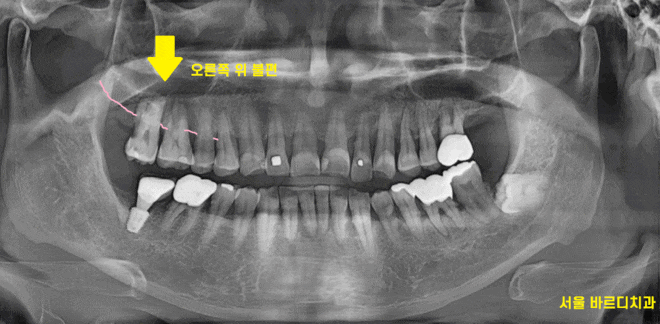

어쨌든 오늘 환자분 검사를 위해 촬영한 x ray

전반적으로 잇몸이 많이 내려가신 상황이었는데요.

221216

잇몸도 내려가고

치아가 전반적으로 닳고 깨진 부위도 관찰됩니다.

불편을 호소하신 오른쪽 치아

x-ray 상에서 잇몸뼈가 많이 내려가